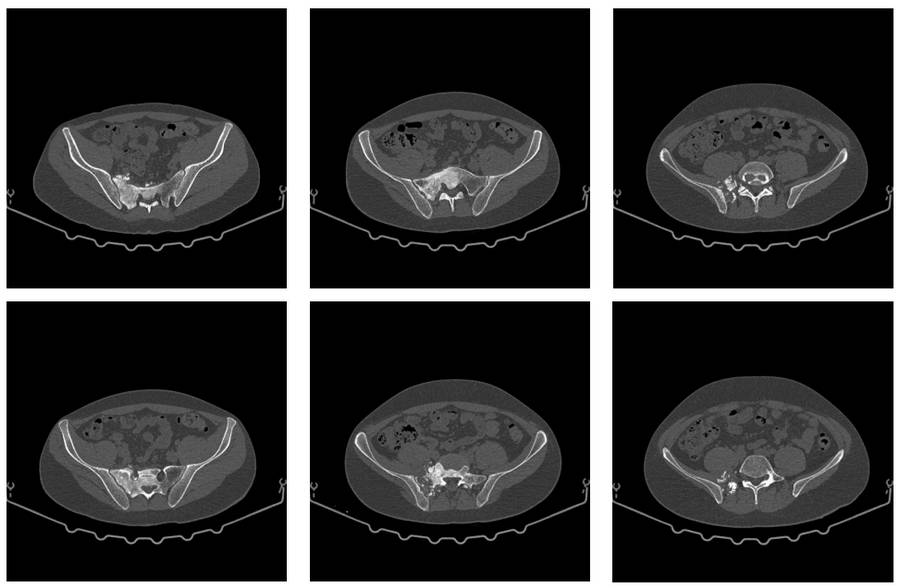

Ameliyat Öncesi: Tomografide sağ sakroiliak bölgede düzensizlik ve sklerozun eşlik ettiği tümör dokusu görülmekte